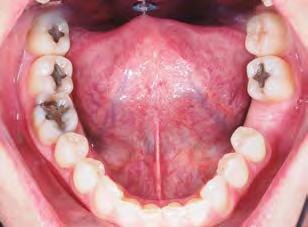

–Corticotomías y Ortodoncia. Ampliando límites del movimiento dental, por la Dra. Aranzazu Senosiain y cols. [50]

–Tratamiento de un caso de Ortodoncia y Cirugía Ortognática con placas preformadas y tecnología 3D, por la Dra. Elena Bonilla Morente y cols. [62]

–Uso del anclaje esqueletal como alternativa eficiente en el manejo ortopédico de clases III por deficiencia de maxilar superior, por el Dr. Carlos Becerra y cols. [74]

–MARPE, una alternativa a la disyunción en el paciente adulto, por el Dr. Enrique Solano y cols. [88]